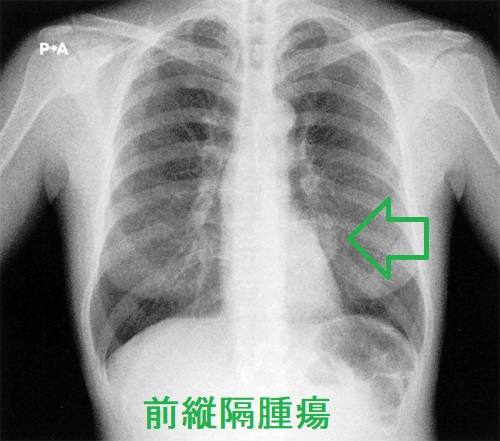

胸腺の過形成による前縦隔腫瘍は胸部レントゲンで写る事があり、肺CT/MRIで確認します。

成人になるにつれて退化する胸腺細胞から胸腺腫が発生します。心臓の前上部、前縦隔にできます。

心臓の上に乗っかるような形態なので、左に多く、CTで見ると、あたかも甲状腺結節・甲状腺腫瘤・甲状腺腫瘍のように見えます。